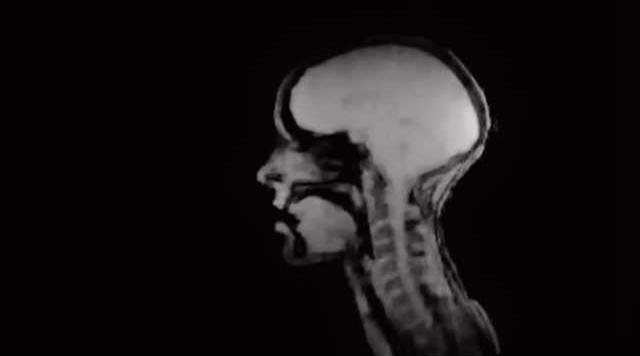

An MRI recording shows a unique and bizarre look at the inside of a woman's head while she performs both normal singing and overtone singing. - photo by Mary Dalrymple

The first thing I said while watching this video is that it was the weirdest thing I'd ever seen. Then I kept watching, fascinated by how freaky, yet genuinely cool, it was to see this inside view of a singing head. And halfway through the video, it got even cooler when Hefele switched from normal singing to her specialty overtone singing, also known as "throat singing" and we got a look at how she's able to make music by basically only moving her tongue.

Fortunately, this MRI recording exists and now we have this interesting video where we can watch how Hefele's tongue creates such distinct notes while her mouth barely moves. Enjoy the video; I bet it's something you never thought you'd be able to see, so thanks, technology, for making the bizarre possible.